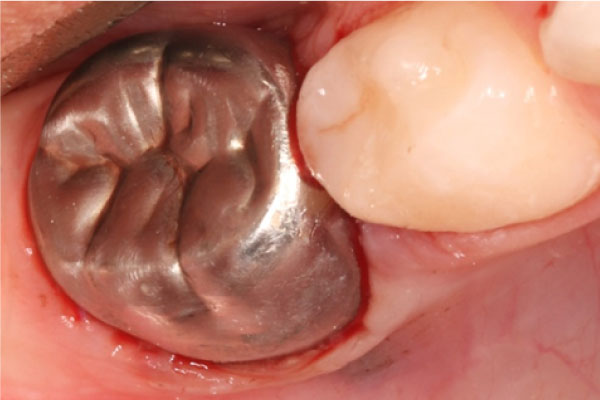

Лечение кариеса молочных зубов: фото До и После

Лечение кариеса молочных зубов имеет принципиальные особенности, учитывающие специфику их строения. Как правило, для лечения используются стеклоиномерные материалы, которые обеспечивают истирание пломбы одновременно с естественным стиранием молочного зуба, а также укрепляют окружающие пломбу ткани. На ранних стадиях кариес можно вылечить и без бормашины, с применением современной технологии ICON, когда композитный материал наносится на поврежденный участок.

Особенности лечения кариеса у детей

Для лечения глубокого кариеса молочных зубов требуется механическое воздействие для вскрытия и очистки кариозной полости. Как правило, препарирование проводится традиционно – бор-машиной. Но есть и современные малотравматичные методики, например водно-абразивное препарирование. Применение специальных пломб, в состав которых входит кальций, фосфор и фтор не только помогает восстановить целостность зуба, но и укрепляет его структуру. На молочные зубы можно ставить разноцветные пломбы – выбирая любимый цвет, ребенок забывает о неприятных ощущениях и лечение превращается в веселую игру.